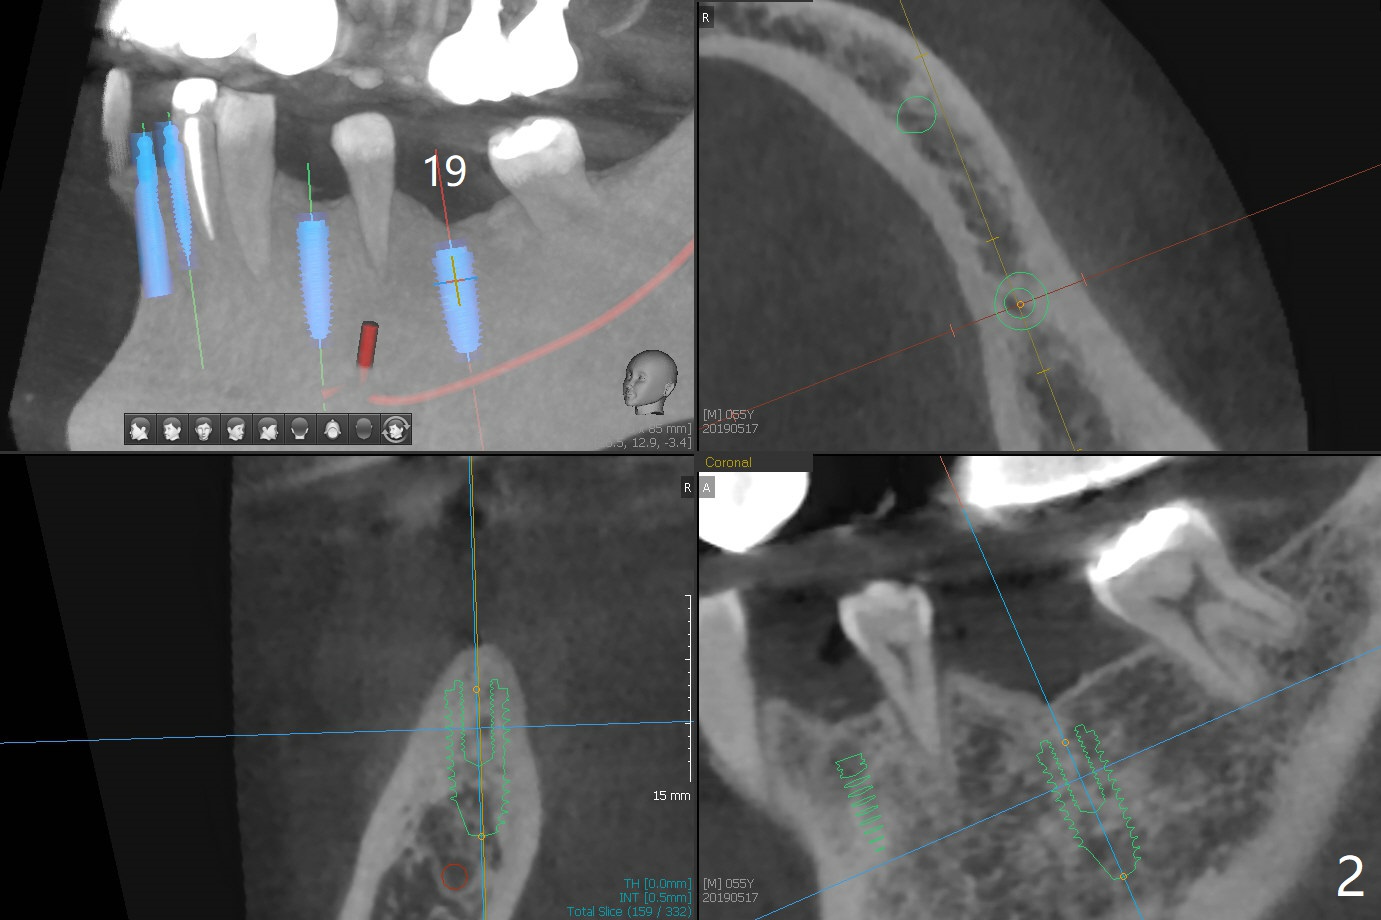

The implants at #11, 14 and 15 are IBS. To reduce the chance of screw loosening, IS guide will be used for better trajectory at #19,21,30. Since the ridge at #21 and 19 is pointed at the top, the implant will be placed deep (Fig.1-4). Bone trimmer will be used prior to pointed drill to avoid drill deflection. Check whether the IS implant driver fits IBS implant well. Try dummy implants first.